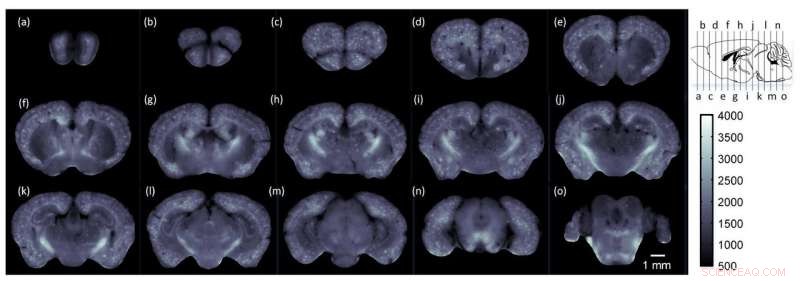

Using cryo-MOST, the researchers acquired a brain-wide map of an Alzheimer mouse model showing that senile plaques had spread to the entire brain. The images are at 1-millimeter intervals from the olfactory bulb to the cerebellum. The specific locations are shown in the upper right insert. Credit: Jing Yuan, Huazhong University of Science and Technology

To demonstrate the ability of cryo-MOST to image the brain-wide distribution of senile plaques, the researchers used it to image a whole brain from a 17-month APP/PS1 mouse model of Alzheimer's disease.

"The images from an aged Alzheimer's disease mouse revealed that senile plaques have spread to the whole brain," said Yuan. "This indicates that the disease not only hurts memory and intelligence, but may also cause an overall deterioration of other brain functions."

The system used in the paper has a lateral resolution of 1.072 microns and an axial resolution of 17.152 microns when detecting fluorescence at a wavelength of 536 nm. The researchers say that these parameters could be further improved by using a better microscope.